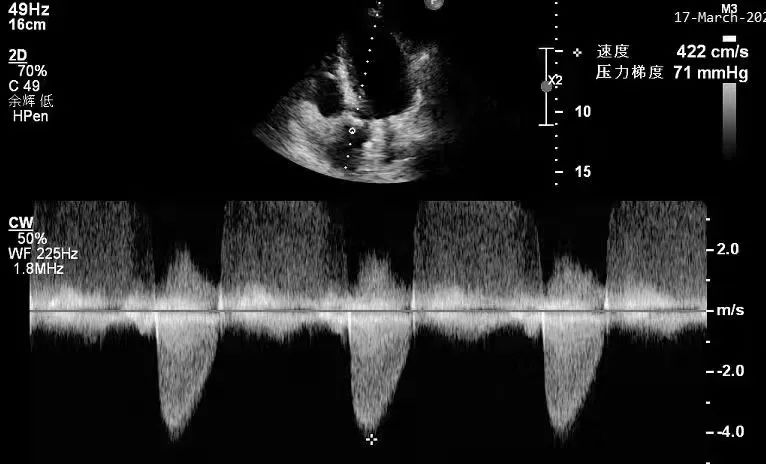

术后超声

术后超声科叶华容主任在手术室为患者进行术后评估,实时超声显示该患者主动脉跨瓣压差由术前的74mmHg显著下降到术后的16mmHg,手术效果立竿见影,患者胸闷、气促症状明显缓解,且无传导阻滞、穿孔等并发症发生,宣告手术圆满结束。